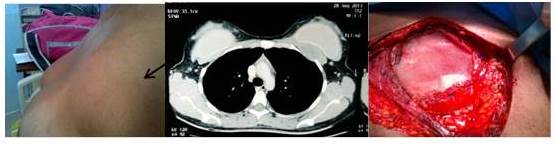

La primera paciente de 21 años de edad, presentó aumento de volumen progresivo no doloroso en mama izquierda, se realizó mastoplastia de aumento 2 años antes, donde se colocó implantes de silicón sin complicaciones. El examen físico inicial de la paciente se observó asimetría en la unión de los cuadrantes superior de mama izquierda, a la palpación se describe tumor de 6 cm x 6 cm duro, fijo a planos profundos no doloroso. El ultrasonido de mama mostró tumor sólido, hipoecoico, heterogéneo de 6 cm x 2 cm x 4 cm sobre la superficie del pectoral mayor, en la mamografía no se observa lesión. La tomografía de tórax con contraste endovenoso reportó una imagen de colección heterogénea con similares dimensiones y en la RMN de mama describe imagen sobre la superficie anterior del pectoral mayor derecho irregular, isointenso en T1 e hiperintenso en T2, a la administración de contraste describe curva de impregnación progresiva. La biopsia con aguja gruesa reporta tumor fusocelular cónsono con fibromatosis extra-abdominal y la inmunohistoquímica mostró inmuno-reactividad positiva para vimentina, y negativa para desmina, CD34 y proteína S100. Con este diagnóstico se realizó resección local amplia de tumor que incluyó el segmento anterior de segunda y tercera costilla más retiro de prótesis, la reconstrucción de la pared torácica se realizó con malla de polipropileno (Figura 1). La biopsia definitiva reportó tumor de 8 cm x 7 cm compatible con fibromatosis agresiva con márgenes superior y medial microscópicamente positivo. Como tratamiento adyuvante recibió radioterapia externa (RT). Posterior a 30 meses de seguimiento la paciente se encuentra libre de enfermedad locorregional y a distancia (Figura 2).